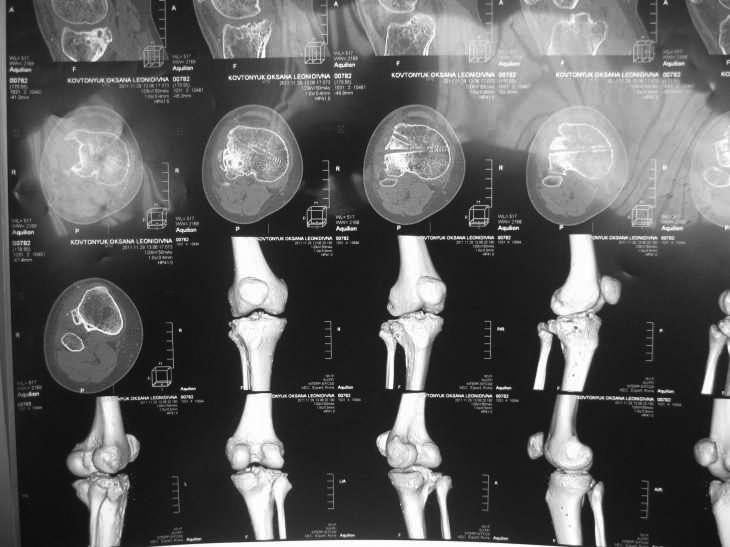

Жалобы на деформацию и нарушение функции правого коленного сустава .Внешний вид –вальгусная деформация на уровне коленного сустава .Коленный сустав стабильный, надколенник при сгибании в правильном положении.

Планируэм провести остеотомию на уровне проксимального метафиза большеберцовой кости .

Вложение не в текстовом формате было извлечено…

Имя     : IMG_0039.jpg

Тип     : image/jpg

Размер  : 27120 байтов

Описание: отсутствует

Url     : http://weborto.net:8080/pipermail/ortho/attachments/20120513/91cb8573/attachment-0003.jpg